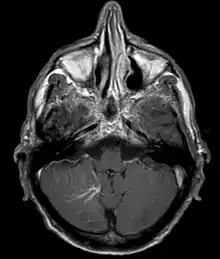

| Developmental venous anomaly in the cerebellum seen on axial contrast-enhanced T1 weighted MRI | |

A developmental venous anomaly (DVA, formerly known as venous angioma) is a congenital variant of the cerebral venous drainage. On imaging it is seen as a number of small deep parenchymal veins converging toward a larger collecting vein.